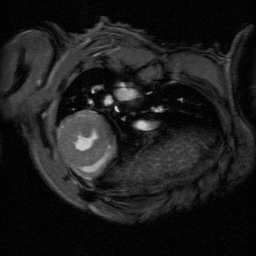

An extremely powerful instrument for most challenging murine imaging studies

The ultra-high field of the BioSpec 152/11 provides extreme sensitivity for greatest resolution. Its streamlined design for mice studies makes handling simple, while its powerful software guarantees best results. It can be equipped with the MRI CryoProbe to increase sensitivity even further and together with the gradient strength of up to 1000 mT/m, highest resolution is achieved. It is built with nitrogen-free Ultra Shielded and helium Refrigerated (US/R) magnet technology for long service intervals

• Crisp and highly resolved images with native gradient strength of 740 mT/m, upgradable to 1000 mT/m

• MRI CryoProbe for exceptional increase in sensitivity